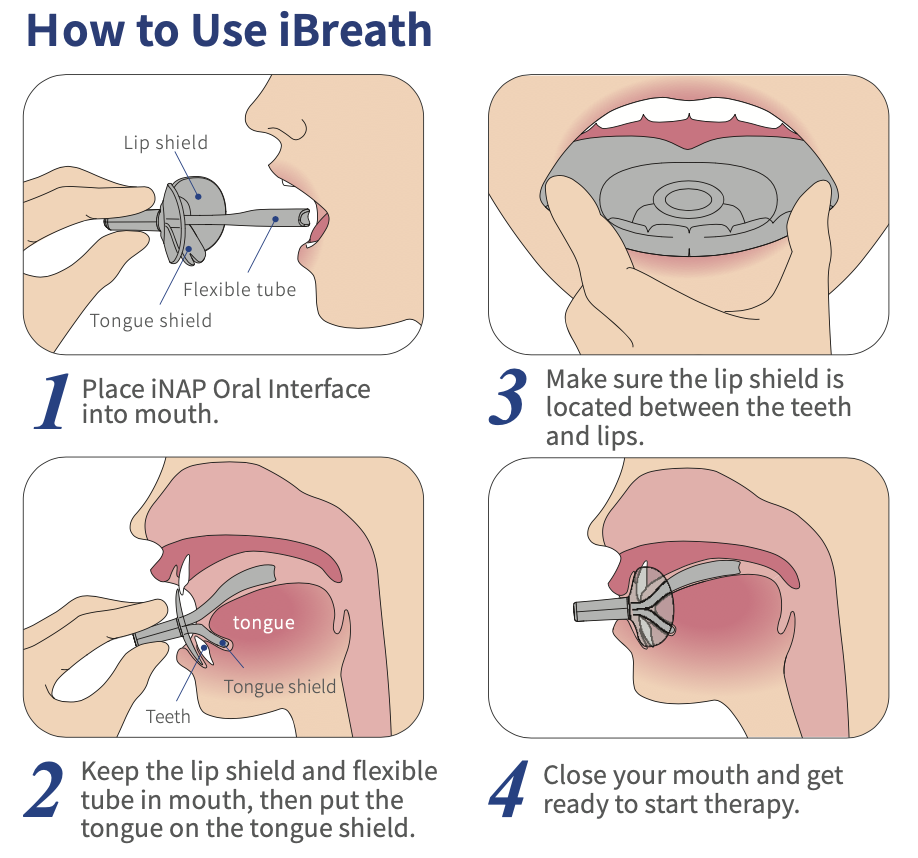

iBreath® is a comfortable device reusing the same design as iNAP’s Oral Interface, with same material.

iBreath is designed to prevent mouth breathing and strengthen the tongue muscles.